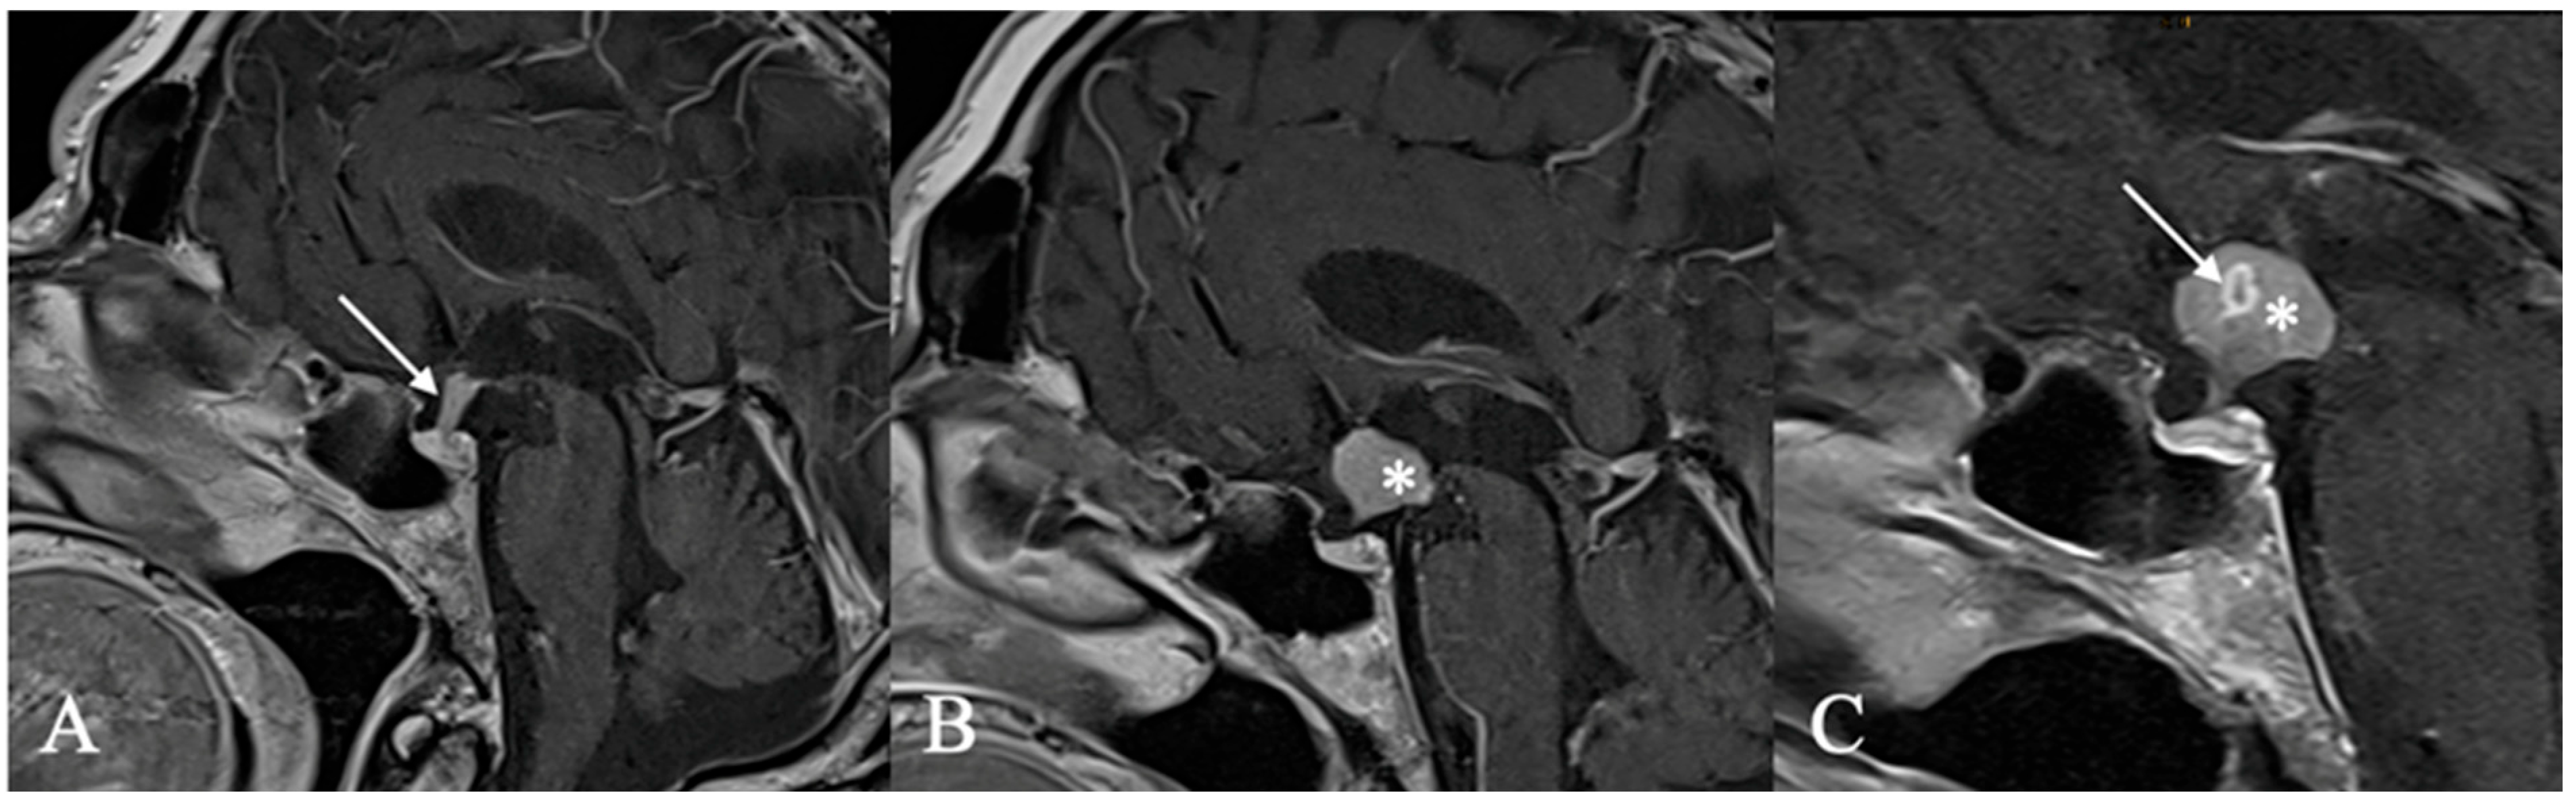

4.2. Differential Diagnoses and Case Presentations